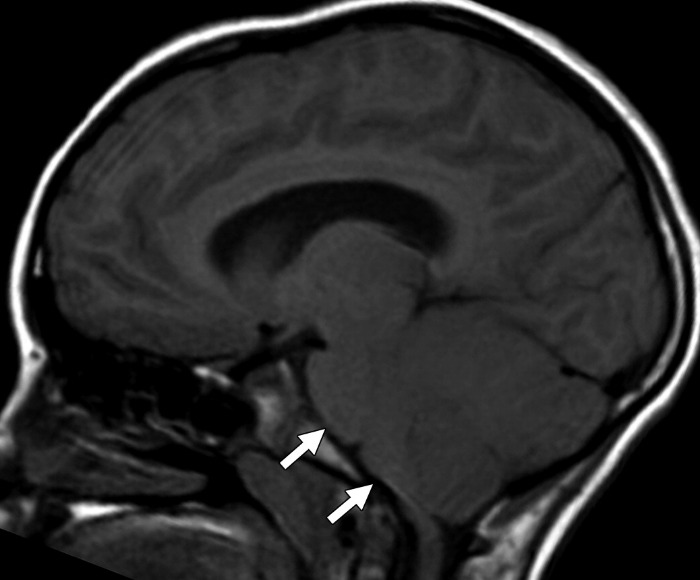

(б) МРТ, Т1-ВИ, сагиттальный срез: у пациента через две недели после развития клинической картины герпетического энцефалита определяется потеря объема мозговой ткани височной доли. Кроме того, визуализируются линейные повторяющие ход извилин участки повышения интенсивности сигнала, которые расположены в структуре коры височной доли и характерные для подострого кортикального кровоизлияния.

Лучевые признаки церебеллита

- диффузное увеличение мозжечка, которое может приводить к окклюзионной гидроцефалии

- локальные или диффузные области повышения сигнала на Т2ВИ и FLAIR

- ограничение диффузии как проявление цитотоксического отека

Корональная Т2ВИ-томограмма показывает гиперинтенсивные области инфарктов в области полосатого ядра слева.

На сагиттальной FLAIR томограмме мозжечок выглядит диффузно увеличенным, оттесняя кпереди структуры ствола.